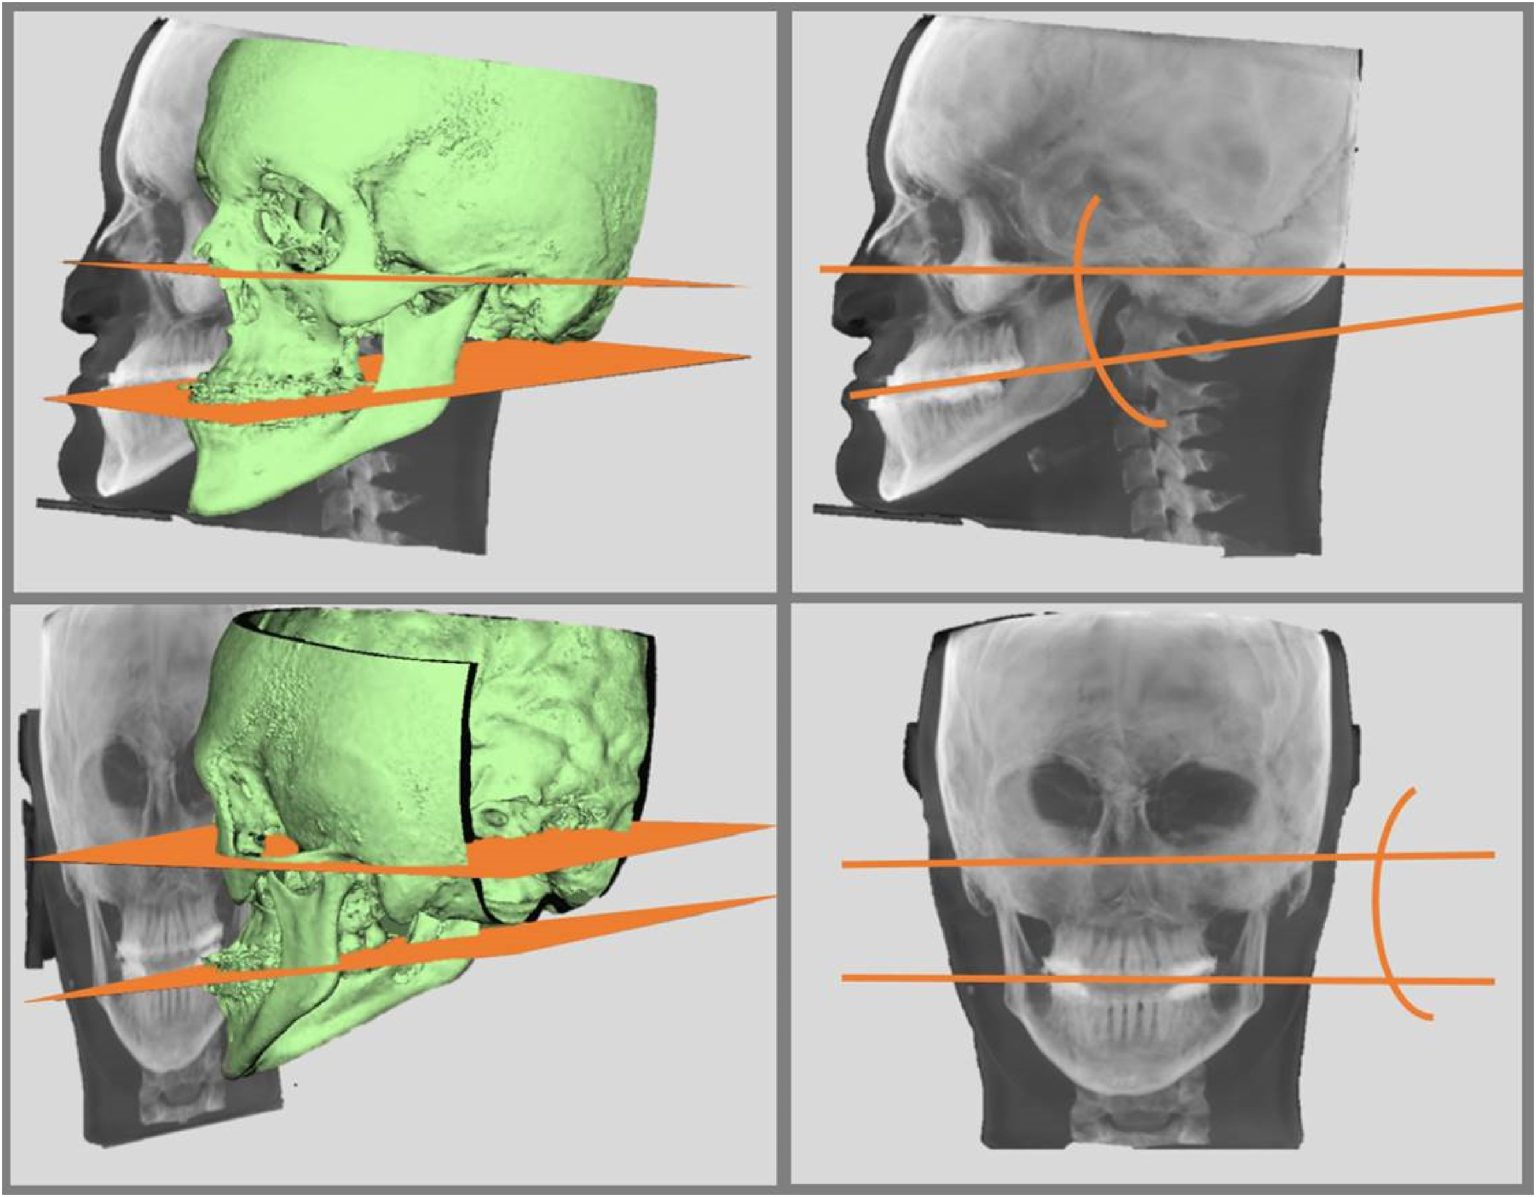

بازسازی سه بعدی

با توسعه فناوری، استفاده از روش‌های تصویربرداری سه بعدی در دندانپزشکی برای تشخیص و بازسازی سه بعدی فک و صورت گسترش یافته...

ادامه مطلب